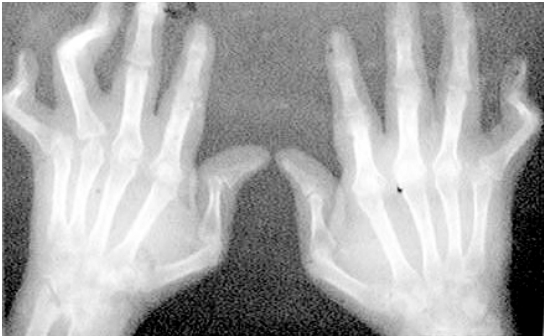

多关节变形的X线片显示

(7)放射学改变:在手和腕的后前位相上有典型的类风湿关节炎放射学改变,必须包括骨质侵蚀或受累关节及其邻近部位有明显的骨质脱钙。

2.X线检查 在发病前几个月内X线检查仅能看到软组织肿胀。随后出现关节周围骨质疏松、关节间隙变窄(关节软骨受累)及边缘侵蚀。X线检查的恶化率与临床恶化率一样,变异很大。但侵蚀作为骨破坏的征象可发生在第一年。一般将类风湿关节炎的X线改变分为四期。

Ⅰ期(早期):①X线检查无破坏性改变。②可见骨质疏松。

Ⅱ期(中期):①骨质疏松,可有轻度的软骨破坏,有或没有轻度的软骨下骨质破坏。②可见关节活动受限,但无关节畸形。③邻近肌肉萎缩。④有关节外软组织病损,如结节和腱鞘炎。

Ⅲ期(严重期):①骨质疏松加上软骨或骨质破坏。②关节畸形,如半脱位、尺偏倾斜,无纤维性或骨性强直。③广泛的肌萎缩。④有关节外软组织病损,如结节或腱鞘炎。

Ⅳ期(末期):①纤维性或骨性强直。②Ⅲ期标准内各条。